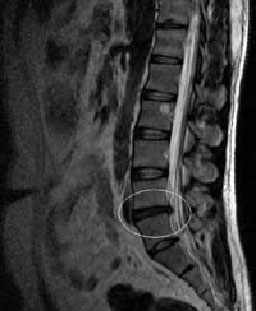

Методом выбора диагностики грыж межпозвонковых дисков в настоящее время является магнитно-резонансная томография (МРТ). При необходимости проводится неинвазивная МР-миелография или инвазивная КТ-миелография.